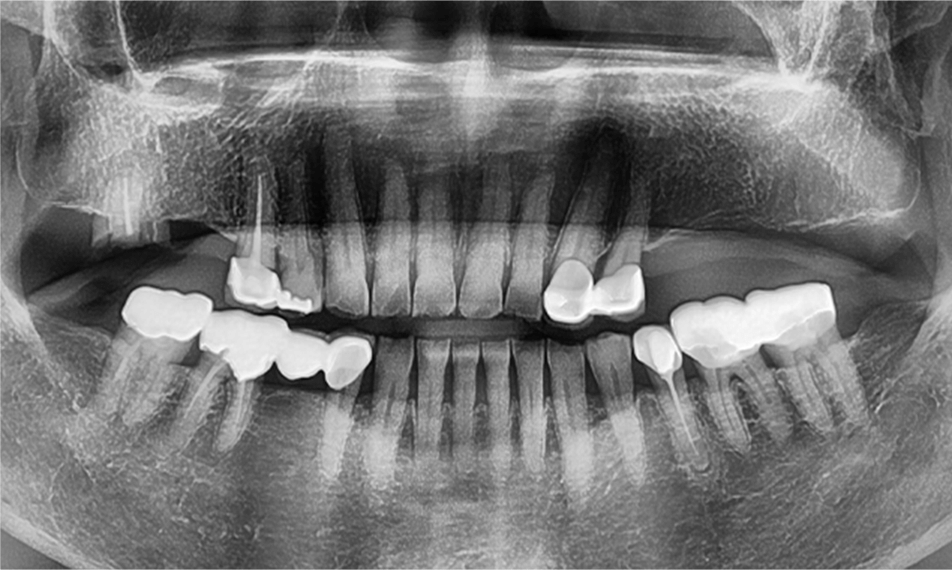

임플란트 치료

• before

• after